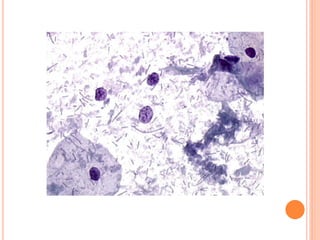

O hormônio que atua na maturação é o estrogênio. As células encontradas no Papanicolaou que sofrem a ação do estrogênio são as células escamosas. Estas células podem ser observadas no Papanicolaou principalmente na fase proliferativa do ciclo menstrual.